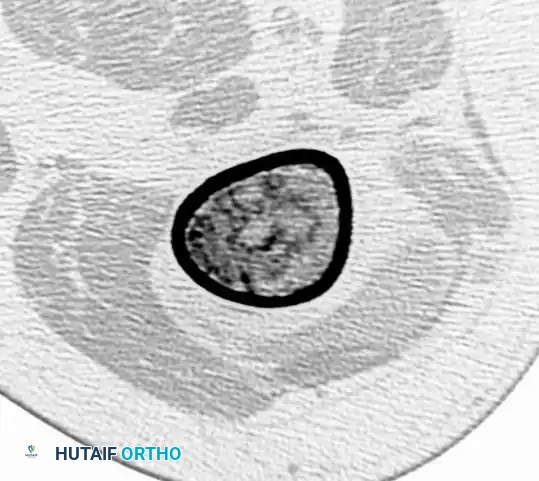

Computed Tomography (CT): CT is the optimal modality for evaluating the integrity of the cortex and quantifying the depth of endosteal scalloping.

CT scan confirming the absence of cortical destruction, supporting the diagnosis of a benign enchondroma rather than a chondrosarcoma. -